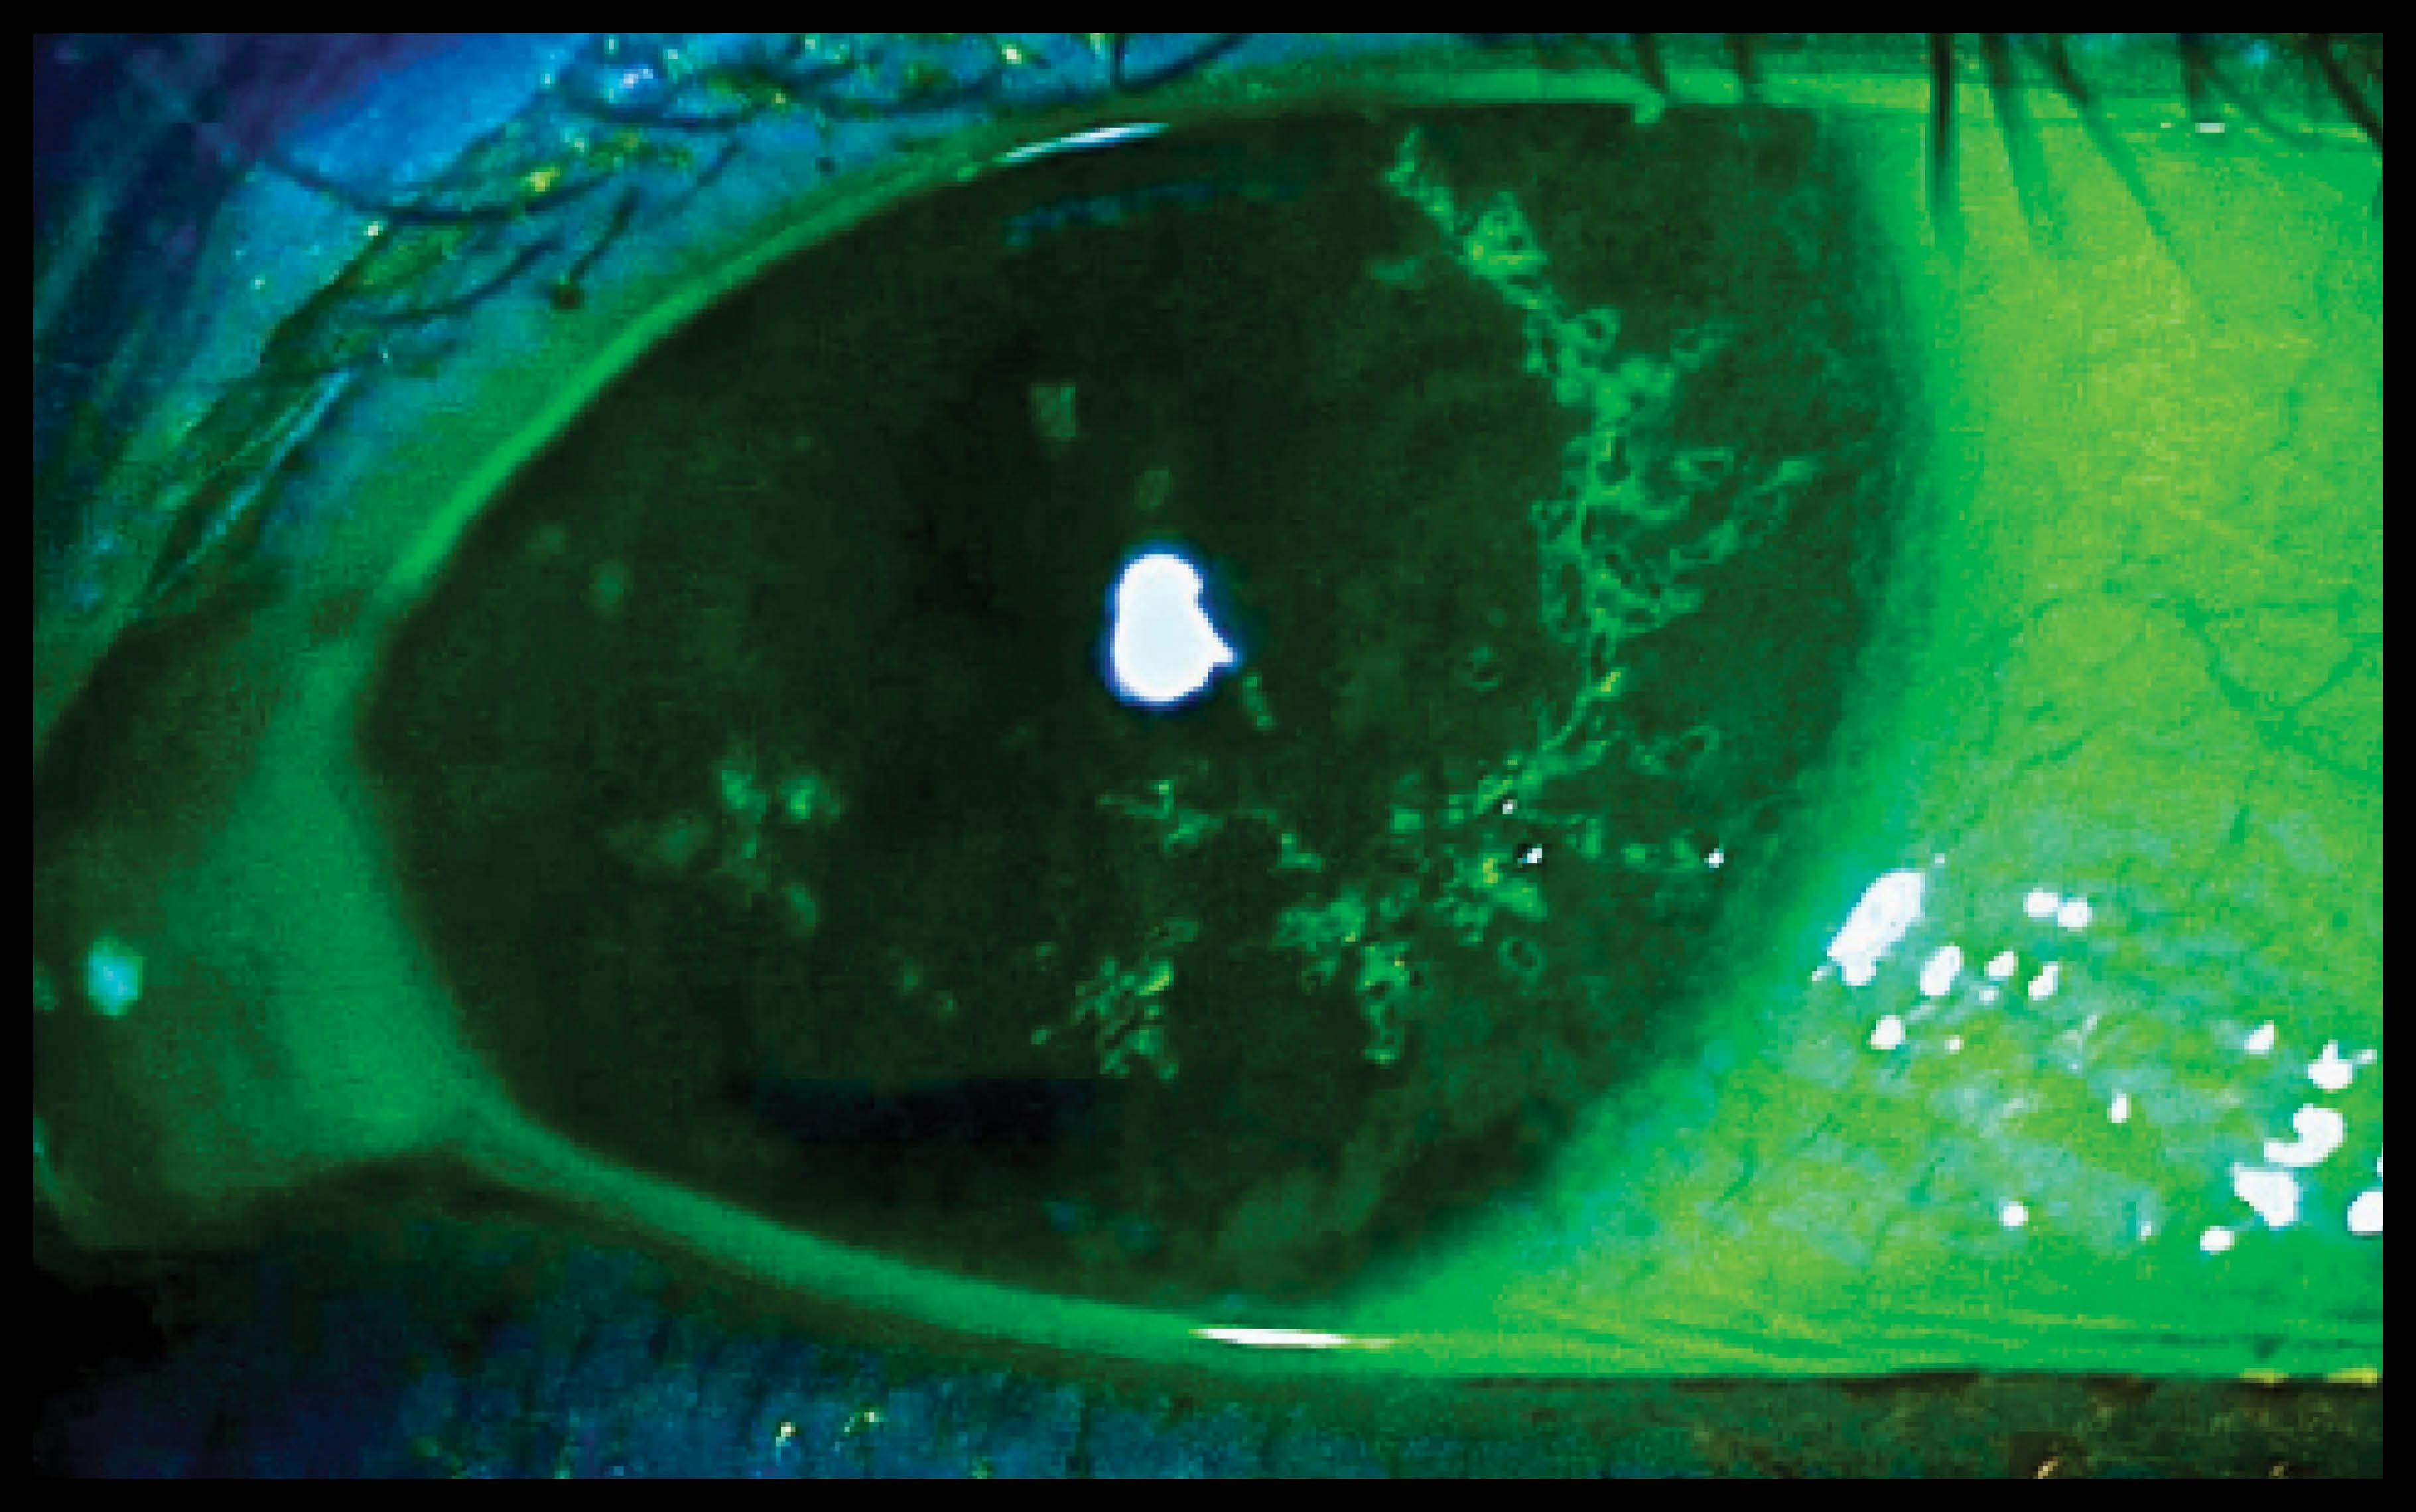

The pseudodendrites caused by HZ (Main Figure and Inset) can be differentiated clinically from true dendrites (herpes simplex viral dendrites), as pseudodendrites tend to be elevated, not ulcerated. Pseudodendrites lack fluorescein staining within the center of the lesion and lack terminal bulbs. Residual corneal hypoesthesia after either of these viral infections can be severe and lead to neurotrophic corneal disease.

Inset. Fluorescein staining of HZO pseudodendrites.